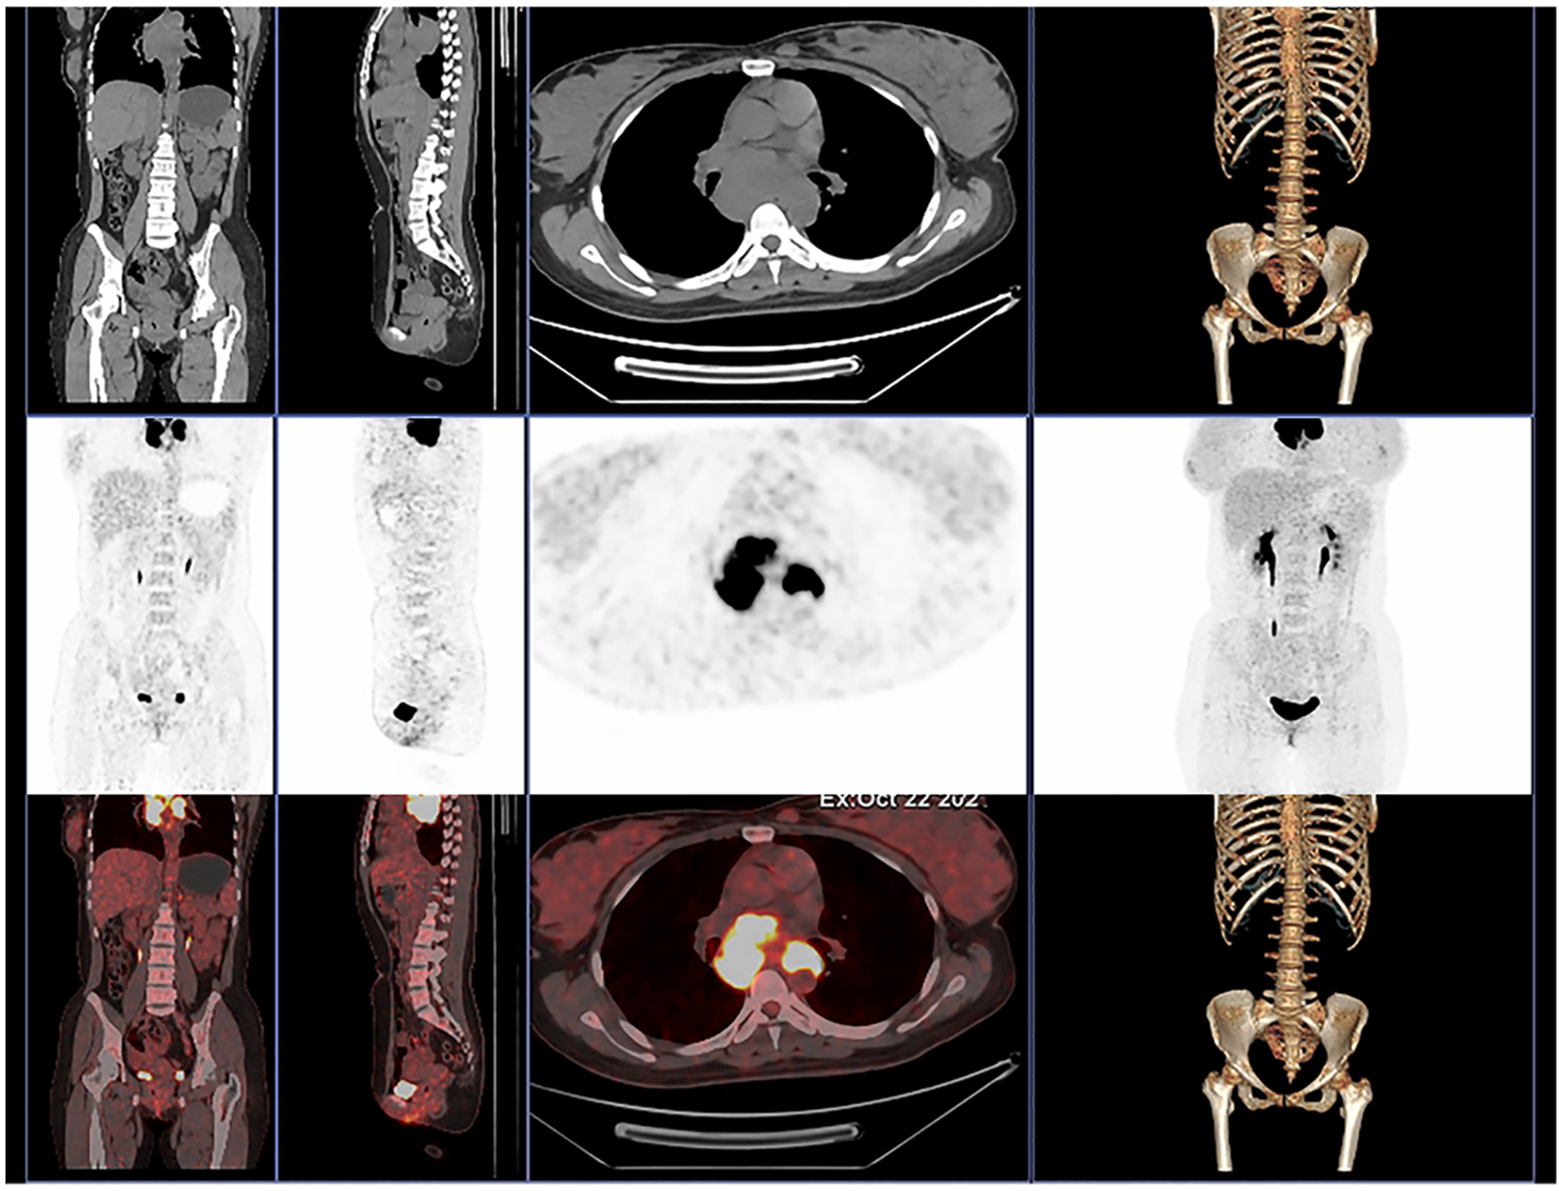

MAL, CD200, and CD23 have been considered as key immunophenotypic markers for the identification of DLBCL and PMBCL (3). The expression of MAL and CD23 in our patient was positive, and PET-CT indicated that there was no distant metastasis, so we can differentiate it from DLBCL. CD20, CD23, CD30, and CD79a were helpful to identify classical Hodgkin’s lymphoma and PMBCL (1, 4). Our patient’s immunohistochemistry showed positive CD20 and CD23 and negative CD30 and Mum-1, so it can be distinguished from classical Hodgkin’s lymphoma. Finally, based on all results of clinical symptoms, pathology tests, and other related examinations, the patient was diagnosed with primary mediastinal large B-cell lymphoma.

Moreover, in order to further evaluate the whole-body condition and choose the treatment, we did 18F-fluorodeoxyglucose positron emission tomography/computed tomography (18F-FDG PET/CT) examination on day 12 (Figure 4). The results indicated multiple enlarged confluent lymph nodes in the mediastinum with significantly increased glucose metabolism (5).

Figure 4

The 18F-FDG PET/CT of our patient shows multiple enlarged confluent lymph nodes in the mediastinum with significantly increased glucose metabolism.